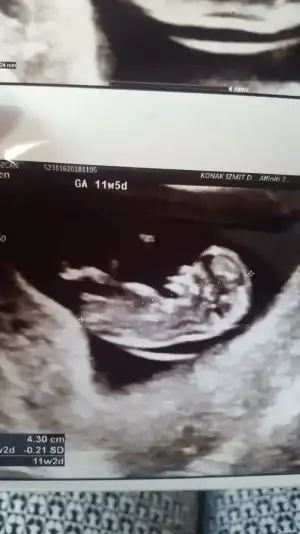

Valla benim 11 . Haftada doktorum kararsz kaldı ama dün devlette ikili test için gittim kız dedi ama yanındaki stajere sordu birde kız dimi diye saçma geldi bana emin olmayarak dedi çünkü benim içime erkek doğuyor ultrason resmine göre

Eklentiler

• 20181106_180612.webp

20181106_180612.webp

11 KB · Görüntüleme: 73